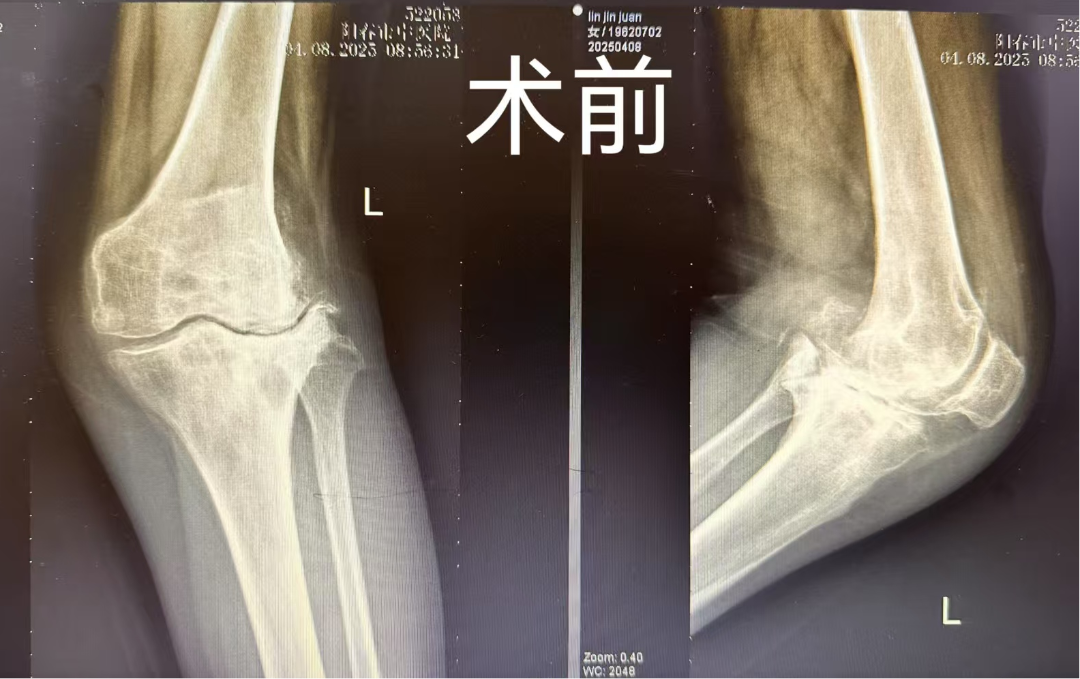

林女士8年前就出现了左膝关节疼痛,近几年疼痛明显加重,并出现了膝外翻畸形明显,行走困难,口服止痛药物后效果也不好,严重影响日常生活。曾拍片检查后被诊断为“左膝骨性关节炎”,并给予左膝关节腔封闭治疗,效果仍差,后经邻居介绍来到我院就诊,检查后以“左侧膝关节骨性关节病”入住我院骨二科。

林女士入院后完善相关辅助检查,谢宝林主任带领骨二科团队就治疗方案展开讨论,根据病史、症状和体征及检查结果,制定了详细的手术方案,建议患者应该进行左侧人工全膝关节表面置换。在给林女士与家属详细讲解手术的必要性后,林女士及家属同意进行手术治疗。

经过进一步恢复治疗,左膝术区切口愈合良好,皮肤无红肿及分泌物,复查左膝DR显示左膝表面置换术后假体位置良好,走路良好,已符合出院指征。林女士于近日出院,终于摆脱了困扰她8年的关节疼痛症状。